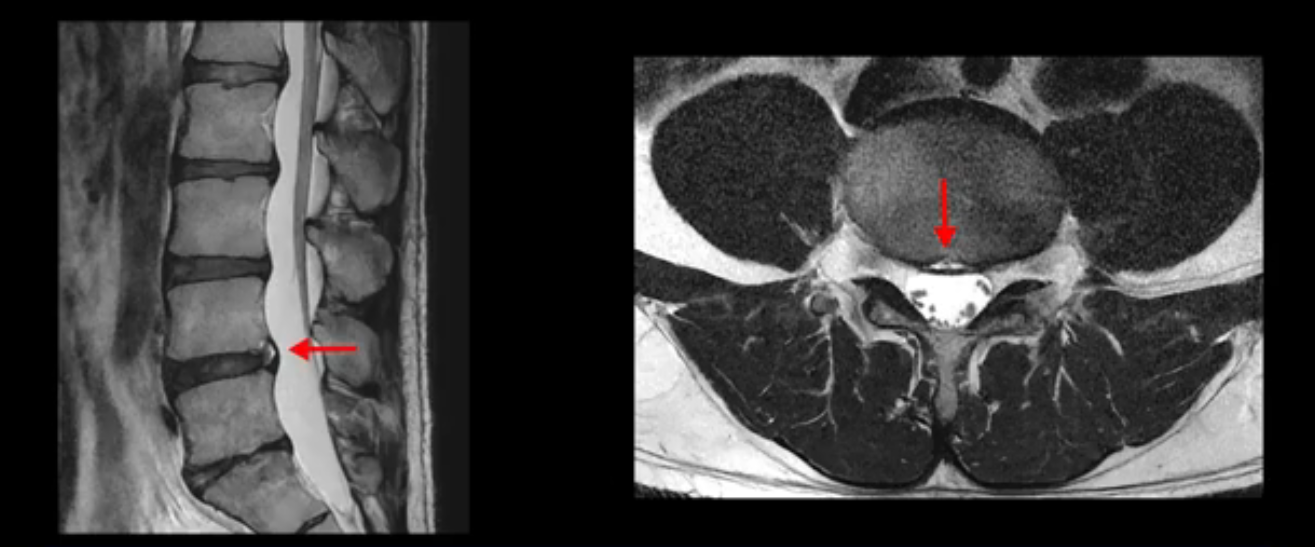

우선 이분 MRI를 보면 허리 모든 마디의 디스크가 퇴행되어 있고

여러 마디의 디스크가 조금씩 밀려나와 보이고, 디스크 섬유륜도 찢어져 보이는 마디도 보입니다.

그런데 이분의 증상과 MRI가 전혀 일치하지 않는데, 왜 그런지 지금부터 자세히 설명드립니다. 이분 증상은 앉으면 엉치와 허리가 심하게 아파 10분 이상 앉는 게 어렵고 양쪽 발가락이 앉아있을 때나 누워있을 때 다 저립니다. 걸을 때도 아파서 10분 걷기도 어렵습니다. MRI를 마디마디 살펴보면 1번 2번은 오른쪽으로 살짝 밀려나온 디스크가 있지만 전혀 심하지 않고, 뒤에 또 설명하겠지만 최근에 밀려나온 급성 디스크가 아니고 오래된 디스크로 판단됩니다.

2번 3번도 비교적 디스크 상태는 좋고 신경 구멍 넓이도 아주 넓습니다.

3번 4번도 마찬가지로 디스크상태 좋아 보이고 신경 눌림 전혀 없어 보입니다.

4번 5번은 가운데로 섬유륜이 찢어져서 디스크가 살짝 밀려나와 있지만 역시나 최근에 찢어지고 밀려나온 걸로 판단되지 않고 오래 전에 찢어진 흔적으로 보입니다.

5번 1번 역시 가운데로 디스크 조금 밀려 나와있지만 신경 공간 넓이는 아주 넓어서 신경 눌림 있을 거라고 예상이 안됩니다.